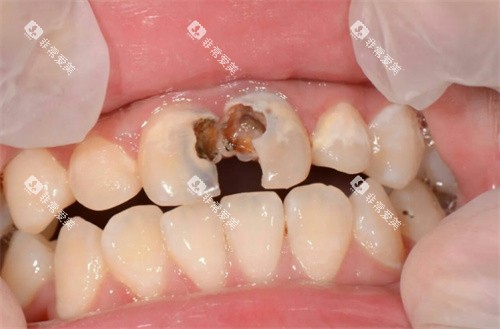

例如,在补牙时,医生会告知患者不同补牙材料的优缺点,让患者根据自己的情况做出选择。

而传统金属牙套在进食时容易残留食物残渣,清洁起来比较困难,长期下去可能会导致龋齿、牙周炎等口腔问题。

这些病例涵盖了各种不同类型的牙齿畸形问题,如牙齿拥挤、龅牙、地包天等。